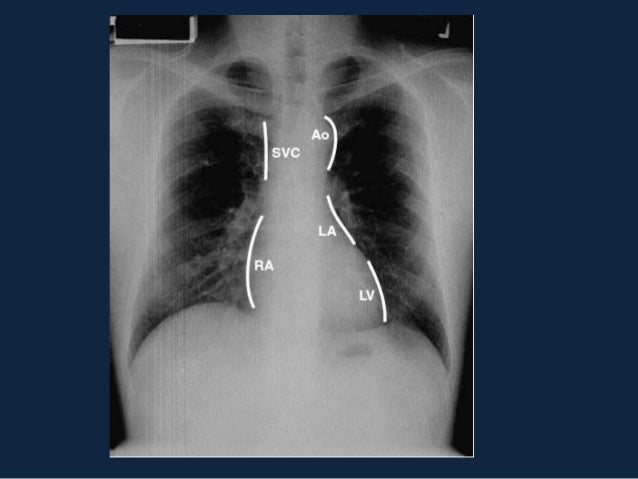

Buongiorno, a mio suocero, a seguito di una lastra ai polmoni, è stato riscontrato uno slargamento mediastino medio Il medico curante lo ha invitato a farsi ricoverare. All'Rx torace puo' evidenziarsi slargamento mediastinico Tra gli esami strumentali sono utili per la diagnosi Eco transesofageo, TAC e RMN Pericardite acuta Dolore acuto, centrotoracico ma di tipo pleuritico, che aumenta con il respiro, si allevia nella posizione seduta con il tronco flesso in avanti. MEDIASTINO PROFILO DESTRO LINEE e RECESSI LINEA PARACAVALE DX La linea paracavale destra consegue, come detto nell’introduzione, alla presenza di un’ interfaccia che vede a stretto contatto una struttura a densità aerea (la porzione paramediastinica del lobo polmonare superiore destro), con la densità “similsolida” della vena cava superiore.

Si parla di sindrome mediastinica quando un processo espansivo interessa il mediastino;. MEDIASTINO PROFILO DESTRO LINEE e RECESSI LINEA PARACAVALE DX La linea paracavale destra consegue, come detto nell’introduzione, alla presenza di un’ interfaccia che vede a stretto contatto una struttura a densità aerea (la porzione paramediastinica del lobo polmonare superiore destro), con la densità “similsolida” della vena cava superiore. Radiografia del torace, che mostra slargamento mediastinico e confermata dalla TC che mette in evidenza masse del mediastino anterore superiore, con coinvolgimento della loggia timica, dei grossi vasi mediastinici, con compressione più o meno marcata della vena cava inferiore e delle vene anonime, della trachea e più caudalmente del pericardio.